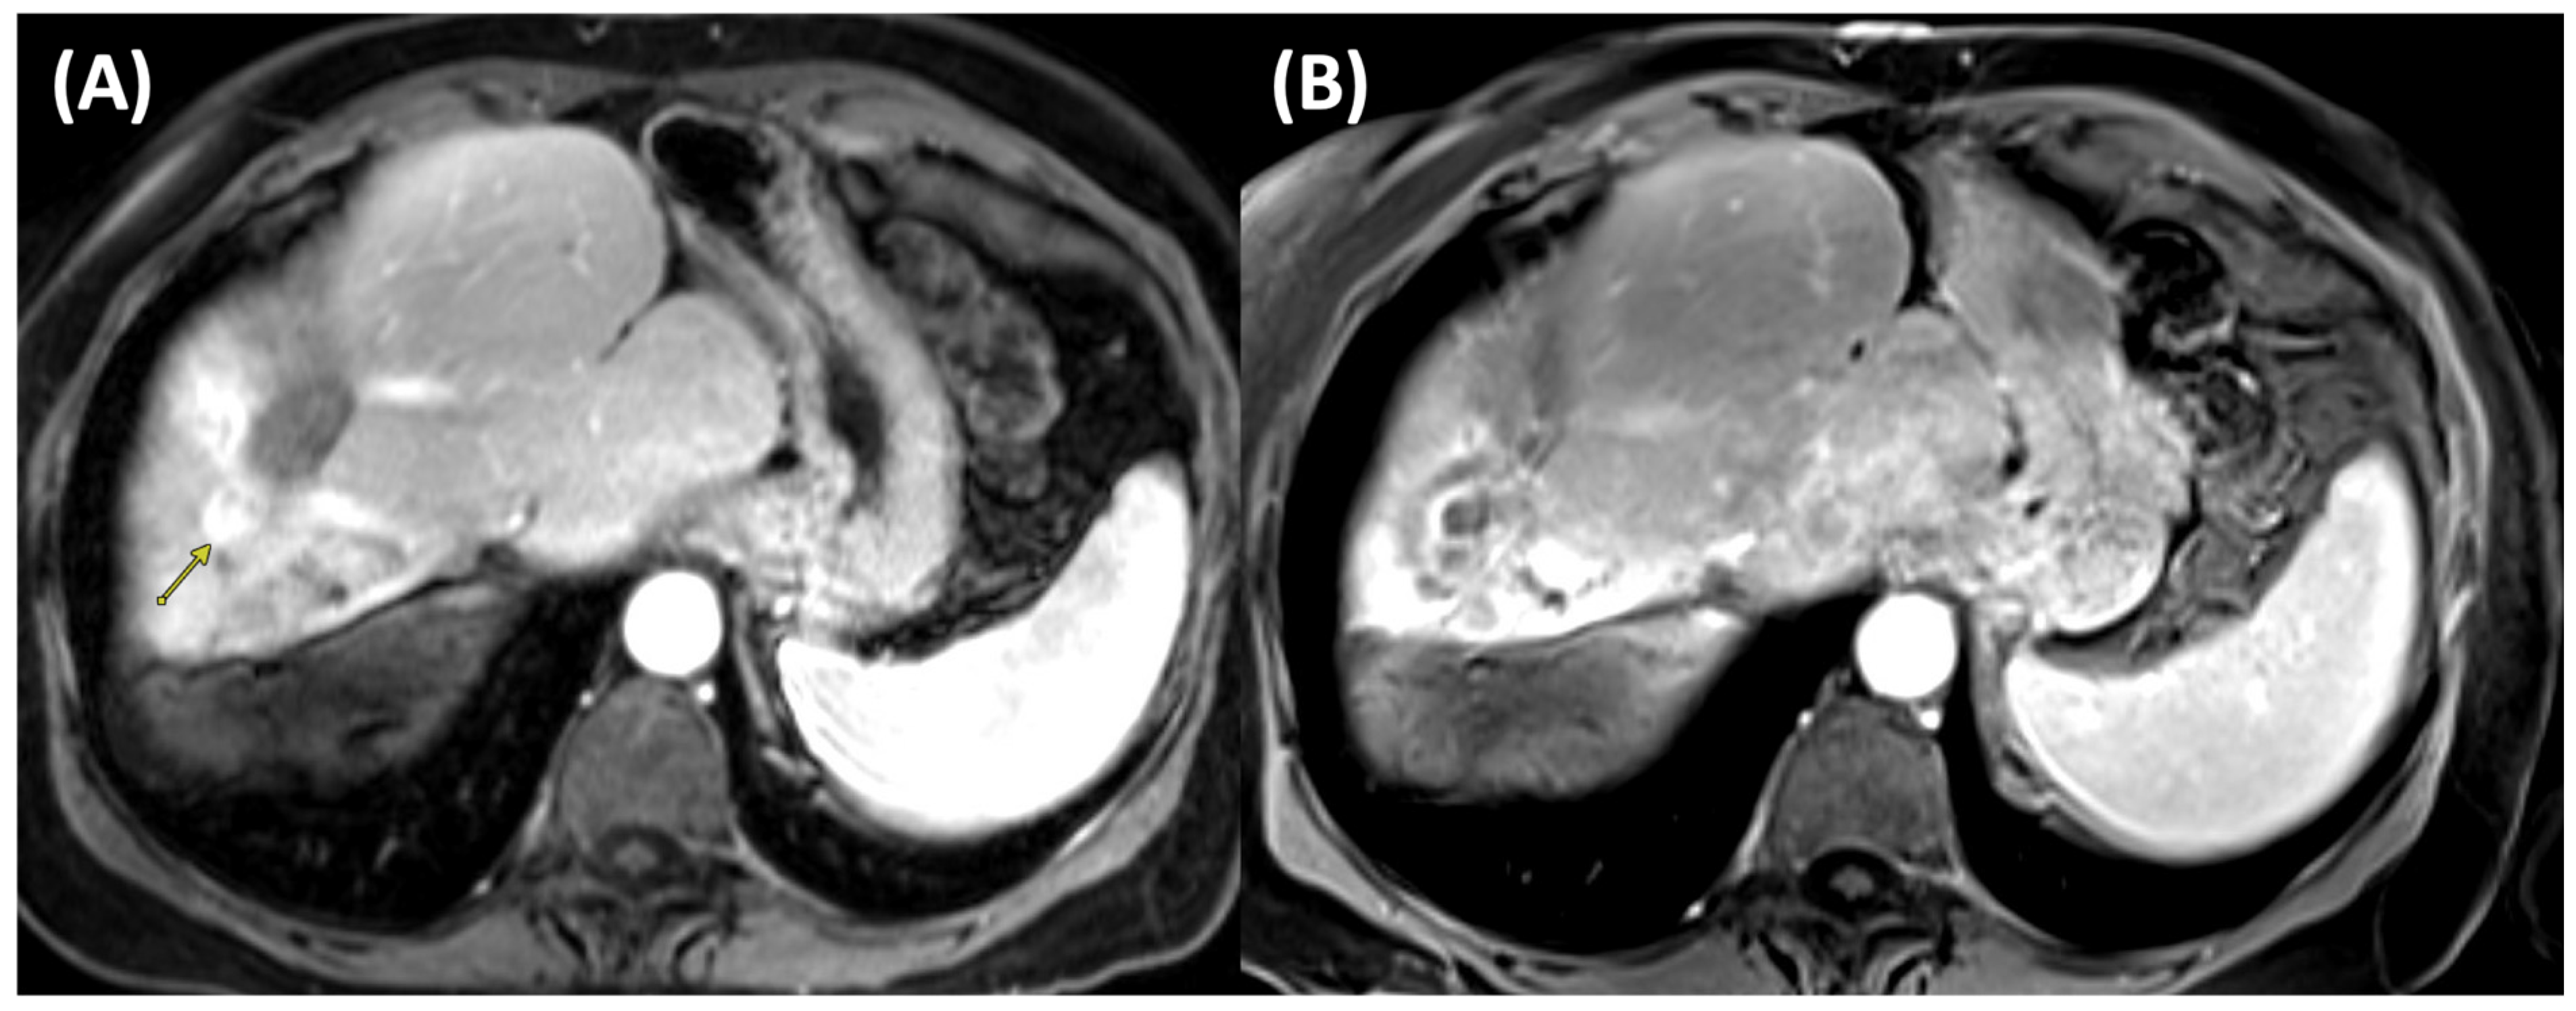

2.2. Microwave Ablation (MWA)